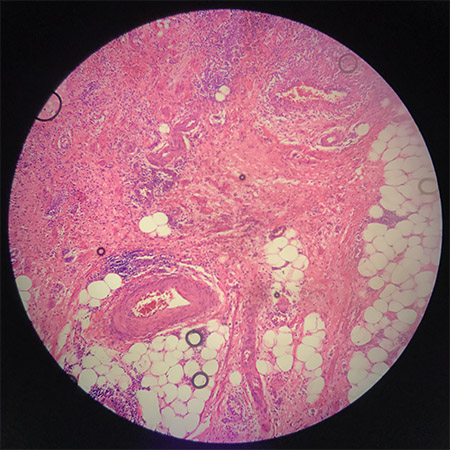

10分钟后

镜下看到的气泡能原地自溶,对使用技术来说,不用担心封出气泡,对于诊断来说看着顺眼不影响看片心情,科室存档不用担心气泡地方褪色。